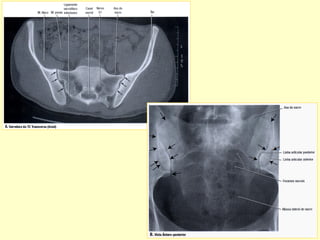

ARTICULAÇÕES SACRO-ILÍACAS

1- RADIOGRAFIAS AP-PERFIL-OBLIQUAS.

2- ESTUDO DINÂMICO.

3- RADIOGRAFIA PANORÂMICA.

5- TOMOGRAFIA COMPUTADORIZADA.